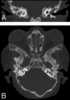

Melnick–Needles syndrome (MNS), also known as Melnick–Needles osteodysplasty, is an extremely rare congenital disorder that affects primarily bone development. Patients with Melnick–Needles syndrome have typical faces (exophthalmos, full cheeks, micrognathia and malalignment of teeth), flaring of the metaphyses of long bones, s-like curvature of bones of legs, irregular constrictions in the ribs, and sclerosis of base of skull.In males, the disorder is nearly always lethal in infancy. [Source: Wikipedia ]